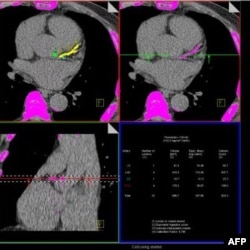

Türkiye ve ABD dahil tüm dünyada ölüm nedenlerinin başında gelen kalp ve damar hastalıkları geliyor. Bu hastalıkların önceden fark edilmesini sağlayacak testler hayat kurtarıyor. Kalp krizi riskini öğrenmenin en kolay yolu uzmanlara göre “kalsiyum skorlaması”. Modern cihazlarla, ilaçsız ve çok kısa sürede yapılabilen kalsiyum skorlaması, dört yıl içinde kalp krizi geçirme riskinin derecesini ortaya çıkarıyor.

Modern cihazlarla, ilaçsız ve derin bir nefes alma süresinde yapılabilen kalsiyum skorlaması, kalp damarlarındaki kireçlenme miktarını ve buna bağlı olan koroner arter hastalığı riskini ortaya çıkarıyor. Kalsiyum skorlaması sonuçları, kişinin gelecek yıllarına ilişkin bilgi veriyor.

Kalsiyum skorlamasında istenen, sonucun sıfır olması. Sonuç sıfır değilse, damardaki kalsiyum birikiminin miktarına göre kişide düşük, orta ya da yüksek derecede kalp damar hastalığı riski olduğu düşünülüyor ve çıkan sonuca göre ilaçla tedaviye başlanıyor. Ciddi bir damar tıkanıklığı olduğu belirlenenlereyse koroner anjiyografi uygulanıyor.

Hastaya ağızdan veya damardan hiçbir ilaç verilmeden, bilgisayarlı tomografiyle sadece bir tutumluk nefes süresinde yapılan kalsiyum skorlaması, uzmanlara göre en önemli tarama testlerinden biri. Modern cihazlarla yapılan ölçümle daha az radyasyon alınıyor.